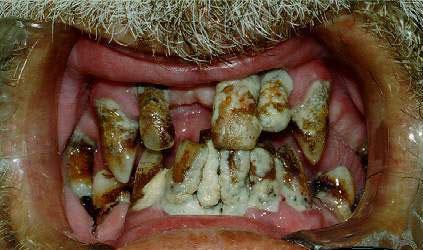

pgc

cette photo traine sur le Net depuis toujours. Le pauvre type à qui elle appartient (appartenait?) est sûrement mort depuis des années!

Xenia2685

c'est clair...je l'ai vue pas plus tard qu'hier, sur un site d'images "droles" (ca, ca ne l'est pas vraiment..)